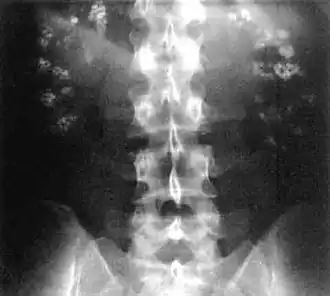

| Bilateral nephrocalcinosis seen on an abdominal x-ray | |

Nephrocalcinosis, once known as Albright's calcinosis after Fuller Albright, is a term originally used to describe the deposition of poorly soluble calcium salts in the renal parenchyma due to hyperparathyroidism. The term nephrocalcinosis is used to describe the deposition of both calcium oxalate and calcium phosphate.[1] It may cause acute kidney injury. It is now more commonly used to describe diffuse, fine, renal parenchymal calcification in radiology.[2] It is caused by multiple different conditions and is determined by progressive kidney dysfunction. These outlines eventually come together to form a dense mass.[3] During its early stages, nephrocalcinosis is visible on x-ray, and appears as a fine granular mottling over the renal outlines. It is most commonly seen as an incidental finding with medullary sponge kidney on an abdominal x-ray. It may be severe enough to cause (as well as be caused by) renal tubular acidosis or even end stage kidney disease, due to disruption of the kidney tissue by the deposited calcium salts.

Nephrocalcinosis is diagnosed for the most part by imaging techniques. The imagings used are ultrasound (US), abdominal plain film and CT imaging.[10] Of the 3 techniques CT and US are the preferred modalities.

- Macroscopic nephrocalcinosis: Occurs when calcification can be seen through X-ray imaging.[1]